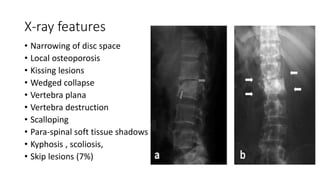

X-ray features

• Narrowing of disc space

• Local osteoporosis

• Kissing lesions

• Wedged collapse

• Vertebra plana

• Vertebra destruction

• Scalloping

• Para-spinal soft tissue shadows

• Kyphosis , scoliosis,

• Skip lesions (7%)